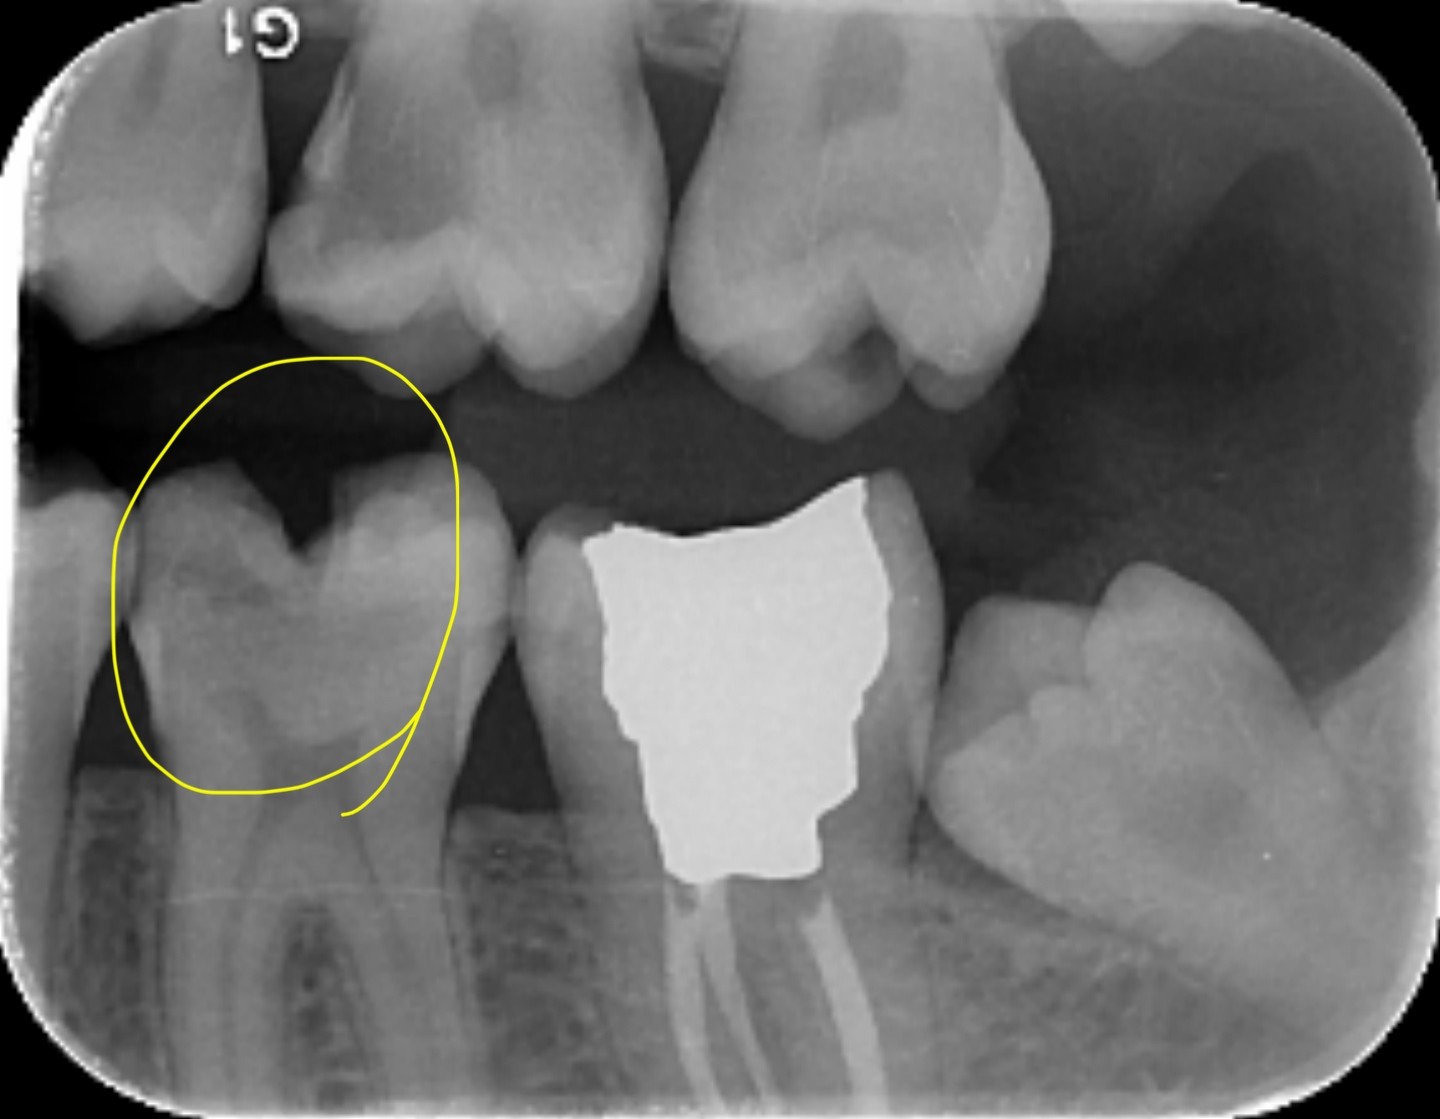

2. In the X ray bellow for which jaw periodontal bone loss is evident?